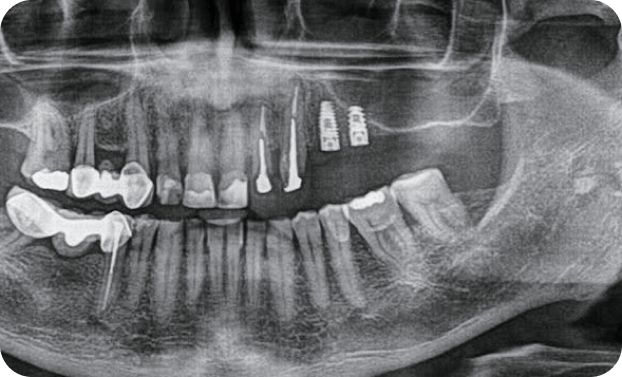

Casos

Instalaciones oral group Instalaciones oral group Instalaciones oral group Instalaciones oral group Instalaciones oral group Instalaciones oral group Instalaciones oral group